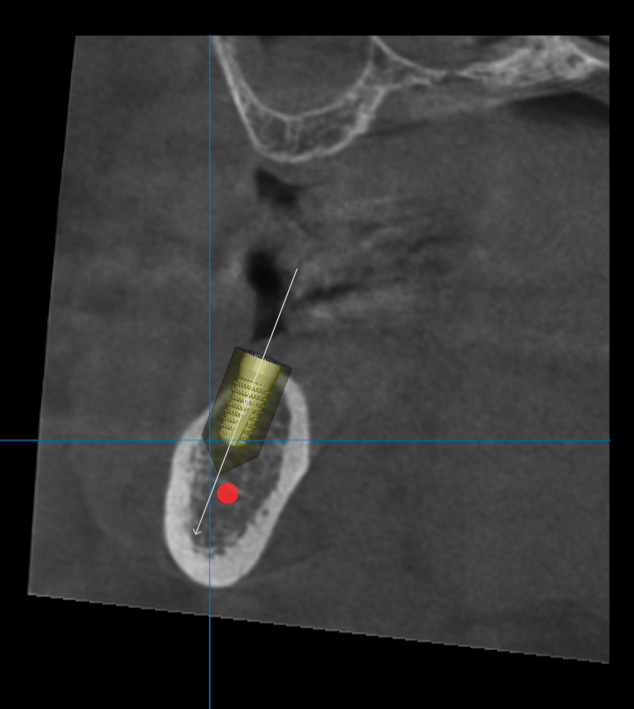

СЛИКЕ